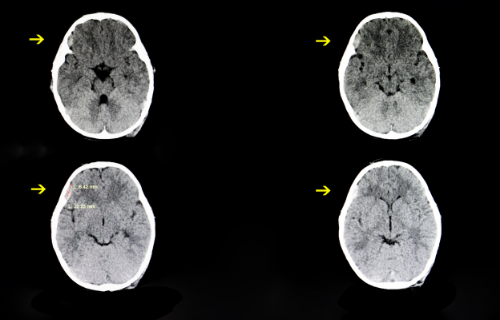

Epidural hematomas can be diagnosed through medical tests. These tests include scans such as non-contrast CT scanning of the head to see skull fractures and the epidural hematoma itself. MRI scans also clearly show an epidural hematoma, though it may not be the go-to test for unstable patients. Toxicology and alcohol blood tests can be done to rule out other causes.

An emergency CT scan of the head must be performed when an acute subdural hematoma is suspected (once the patient is stabilised, of course). A non-contrast CT of the head is also effective in making a diagnosis. Drug and alcohol screenings are also optional tests to rule out other causes.